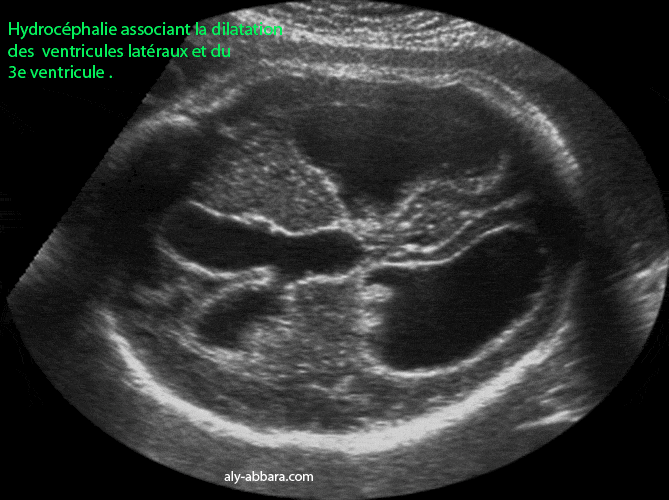

Hydrocéphalie et porencéphalie

Foetus âgé de 30 SA

Image échographique montrant, sur un coupe transverse puis sur une coupe transverse et oblique du cerveau fœtal, une hydrocéphalie associant la dilatation des ventricules latéraux et le 3ème ventricule avec une porencéphalie sous forme d'une zone hypo-échogène, à contour irrégulier, situé dans le lobe frontal du cerveau et mesurant 11 x 17 mm de diamètre.